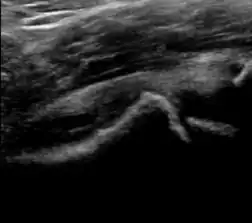

During childhood, ultrasound is a quick method to assess hip pain and quite often may be used to avoid use of irradiating techniques, such as radiography or CT. Ultrasound allows evaluation of joint effusion, synovial thickening and neovascularity, the bone/cartilage contour, and the femoral head-neck alignment. Although sonography is extremely sensitive in detecting increased synovial fluid, it is nonspecific and cannot be used with accuracy to determine the type of fluid. Transient synovitis of the hip, despite being the most frequent cause of pain in children between 3 and 10 years, remains a diagnosis of exclusion. It usually shows anechoic fluid, but echogenic fluid can also be found. The effusion is considered pathologic when it is measured at >2 mm in thickness. The differential diagnosis is wide, including osteomyelitis, septic arthritis, primary or metastatic lesions, LCPD, and SCFE. Discrimination from septic arthritis is challenging, often requiring joint aspiration. In septic arthritis, US is able to demonstrate a hip joint effusion, synovial thickening, and cartilage damage, although the appearances are nonspecific.[1]

A step between the head and the physis can be detected in children with SCFE, while abnormalities in the femoral head contour may suggest the presence of LCPD. In both cases, radiographs are mandatory to confirm diagnosis and severity (Figure 12).[1]

Figure 12:

Normal ultrasound appearance of the femoral head-neck junction. -

Joint effusion in transient synovitis of the hip. -

Flattening of the femoral head in a patient with Perthes disease. -

Step in the femoral head-neck junction in a patient with SCFE.